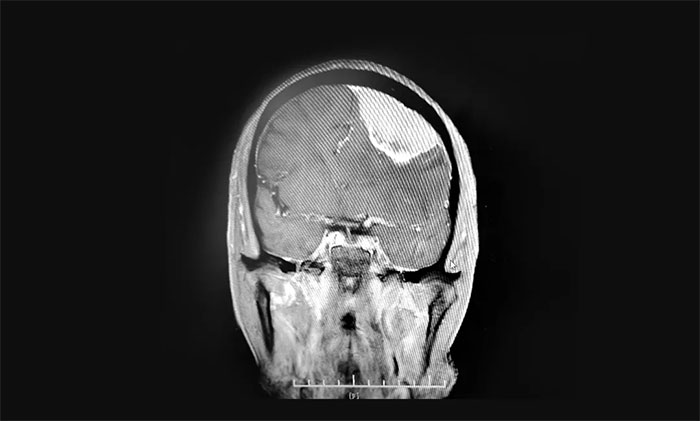

入院检查,头颅MRI提示:左侧额叶大脑凸面可见巨大团块状异常信号,周围可见明显水肿信号,胼胝体明显肿胀,临近左侧脑室受压向右侧移位,中线结构轻度右移,病灶大小约7.2×3.3×3.2cm。

▲ 肿瘤位于左侧额部